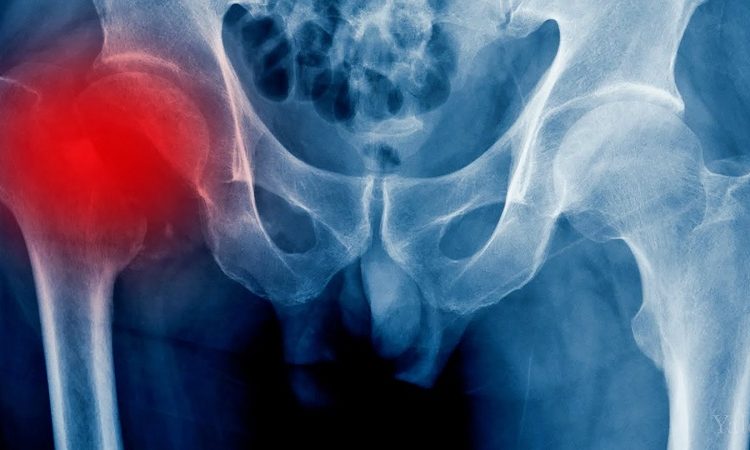

Avascular necrosis harms bone tissue. Blood flow reduces within the hip. Bone cells without supply soon fail. Arthritis also wears the cartilage. The smooth surface becomes rough. Every movement then brings harsh pain. The body weakens further each day. Patients often lose mobility and peace. Simple walks feel like hard work. Conventional methods mask pain briefly. Surgery brings risk and long recovery. Stem cell care seeks another path. This path supports internal growth. Healthy tissue can then return. Hope rises for a better life.